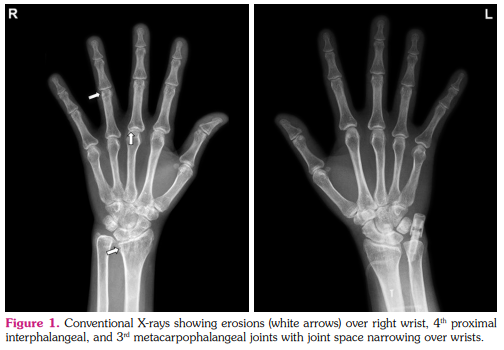

She had refractory RA activity under MTX 15 mg/week, prednisolone 5 mg/day, and sulfasalazine (SAZ) 2 g/day. Conventional X-rays demonstrated erosions over right wrist, proximal interphalangeal and metacarpophalangeal joint areas with joint space narrowing over wrists (Figure 1). The RTX therapy with a regimen of 1 g x two fortnightly infusions every six months was initiated from 2016, with a total of 20 infusions until the end of 2020. There were completely depleted circulating CD19-positive B cells (0/µL) after two infusions, normalized ESR/CRP levels with a reduced DAS28 to 2.99 after four infusions, followed by negative anti-AQP4 (1 U/mL, normal reference below 3 U/mL), anti-CCP (below 7 U/mL), and RF (below 20 IU/mL) levels. She had an improved ophthalmological vision to decimal visual acuity 0.06/0.04 (right/left) in 2019. After 20 infusions, the DAS28 further improved to 2.10 and MTX doses were tapered to 7.5 mg/week without using SAZ. Except for initial infusion-related reactions, no adverse effects were observed during RTX therapeutic period. A written informed consent was obtained from the patient for all diagnostic and therapeutic procedures.